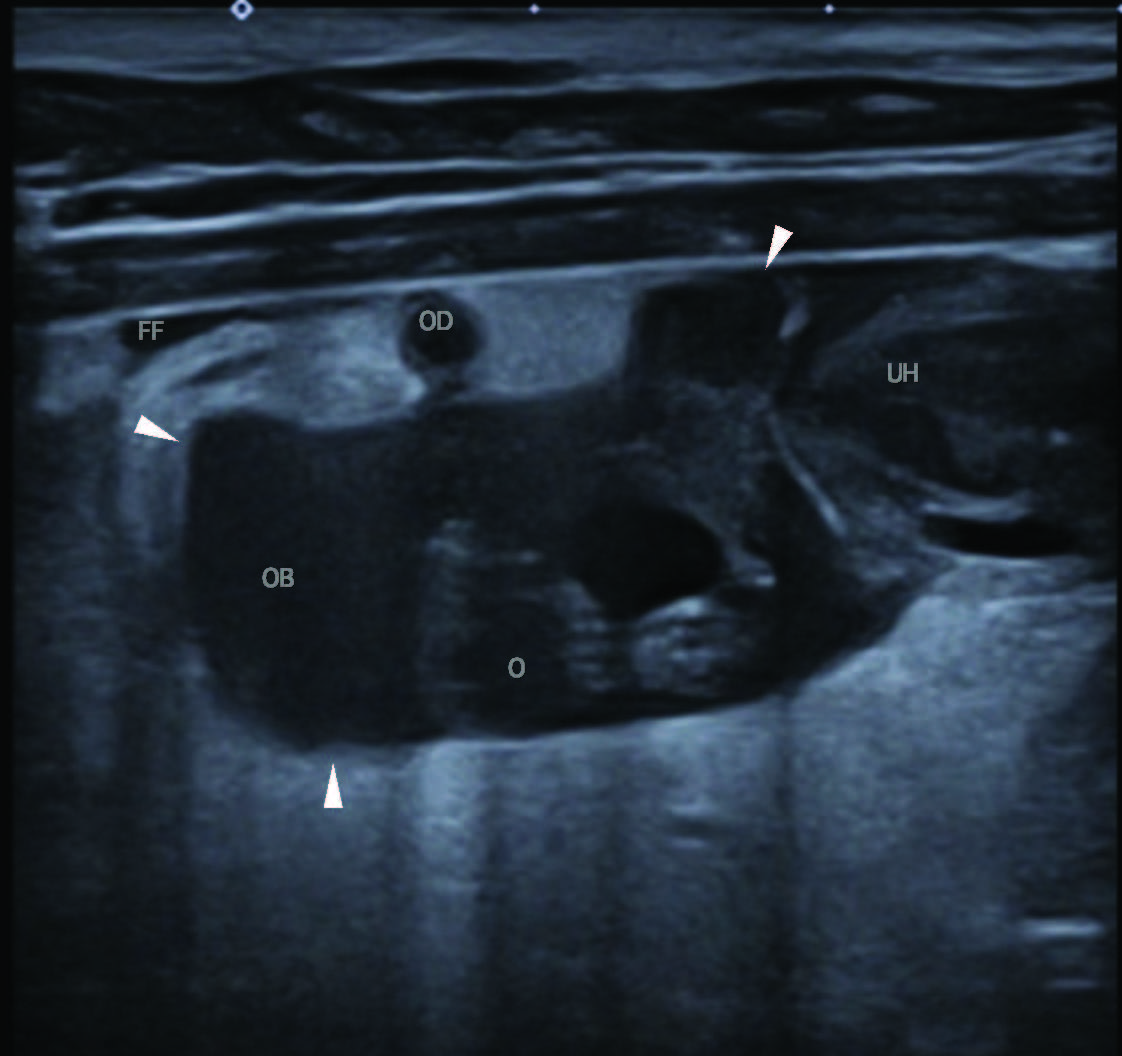

右侧子宫角卵巢端前方并包绕右卵巢处,可见一个25 mm、边界清楚但形态不规则的病灶,内为轻度回声液体,符合卵巢囊积液;邻近腹膜中等度高回声,伴少量游离回声性积液(图3)。子宫角旁尚有少量游离无回声液。

图3. 使用高频线阵探头B模式,在左侧卧位进行的腹部超声纵切面检查。图像左侧为头侧。右侧子宫角卵巢端(UH);右侧卵巢可见结节性病灶(O),周围环绕一界限清晰、充满液体的病灶,符合右侧卵巢囊(OB;箭头示卵巢囊边界)。该病灶周围腹膜脂肪回声增强,并伴有少量游离液体(FF)。图中横向显示的纤细弯曲管状结构,符合输卵管(OD)。

沿卵巢至子宫角卵巢端纵行,可见一略弯曲管状结构(最大径4 mm),无彩色多普勒信号,考虑为输卵管(图3、4)。此外,双卵巢均见多个圆形结构,符合黄体。病灶周围血供保留彩色多普勒信号。